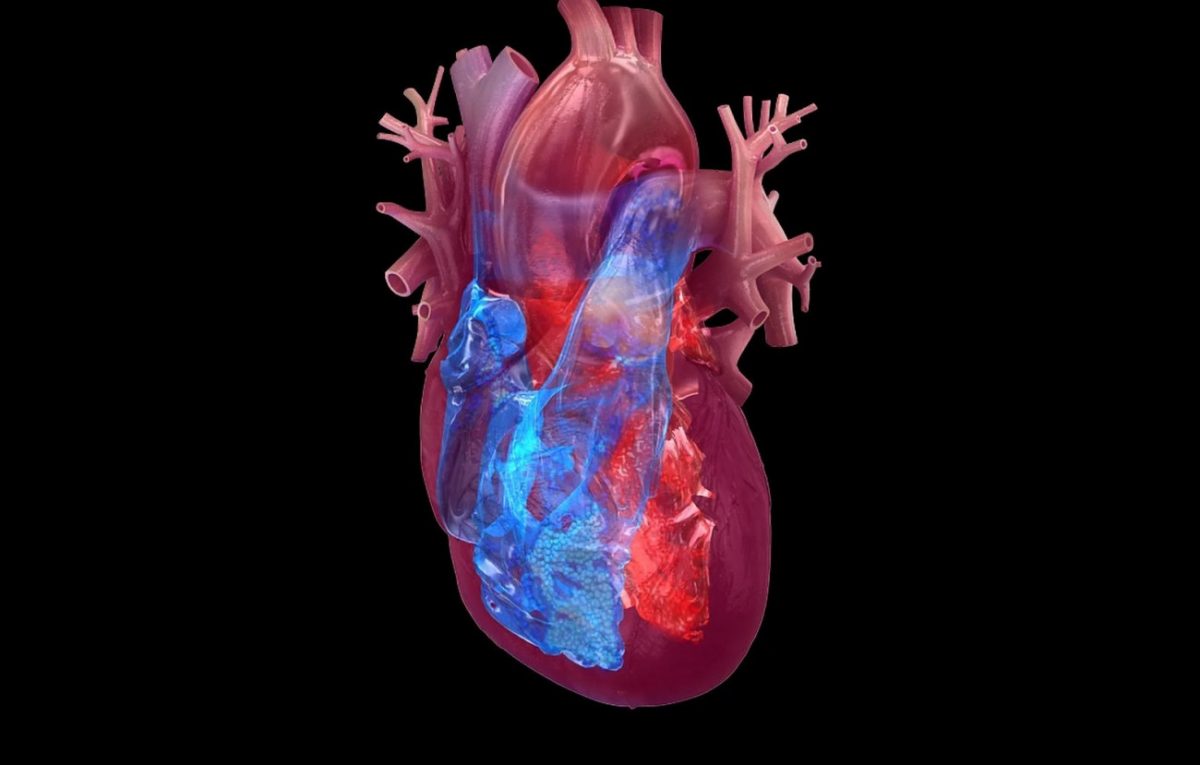

Η καρδιά έχει τον δικό της «εγκέφαλο»

Νέα διεθνής μελέτη με επικεφαλής έλληνα επιστήμονα έδειξε ότι η καρδιά διαθέτει έναν «μίνι-εγκέφαλο» ο οποίος ελέγχει τον καρδιακό ρυθμό. Το εύρημα αναμένεται να οδηγήσει σε καινούργιες θεραπείες για τις καρδιοπάθειες.

Νέα μελέτη ερευνητών του Ινστιτούτου Καρολίνσκα στη Σουηδία και του Πανεπιστημίου Κολούμπια στις ΗΠΑ με επικεφαλής έλληνα επιστήμονα έδειξε ότι η καρδιά διαθέτει έναν δικό της «μίνι-εγκέφαλο» – ένα ολόδικό της νευρικό σύστημα το οποίο ελέγχει τον καρδιακό παλμό. Η καλύτερη κατανόηση αυτού του συστήματος το οποίο είναι πιο πολύπλοκο από ό,τι πιστευόταν αναμένεται να οδηγήσει σε νέες αποτελεσματικότερες θεραπείες για τις καρδιοπάθειες.

Επί μακρόν εθεωρείτο ότι η καρδιά ελέγχεται αποκλειστικά από το αυτόνομο νευρικό σύστημα το οποίο μεταδίδει σήματα από τον εγκέφαλο. Το νευρικό δίκτυο της καρδιάς το οποίο έχει την «έδρα» του στα επιφανειακά στρώματα των καρδιακών τοιχωμάτων, πιστευόταν ότι είναι μια απλή δομή η οποία μεταφέρει στην καρδιά τα σήματα του εγκεφάλου. Ωστόσο πρόσφατες μελέτες έχουν δείξει ότι η λειτουργία του καρδιακού νευρικού συστήματος είναι πιο πολύπλοκη.

Τώρα οι επιστήμονες με επικεφαλής τον δρα Κωνσταντίνο Αμπατζή, κύριο ερευνητή και λέκτορα στο Τμήμα Νευροεπιστήμης του Καρολίνσκα ανακάλυψαν ότι η καρδιά διαθέτει το δικό της πολύπλοκο νευρικό σύστημα το οποίο είναι ζωτικής σημασίας για τον έλεγχο του ρυθμού της, όπως ανέφεραν σε δημοσίευσή τους στο επιστημονικό περιοδικό «Nature Communications».

«Αυτός ο «μικρός εγκέφαλος» της καρδιάς κατέχει ρόλο-«κλειδί» στη διατήρηση και στον έλεγχο των καρδιακών παλμών, ρόλο παρόμοιο με εκείνον που έχει ο εγκέφαλος σε ό,τι αφορά τον έλεγχο ρυθμικών λειτουργιών όπως η αναπνοή και η κίνηση» εξήγησε σε σχετικό δελτίο Τύπου για τη μελέτη ο δρ Αμπατζής.

Tα κυκλώματα της καρδιάς αποδεικνύονται πιο περίπλοκα από ό,τι νομίζαμε

Μάλιστα οι ερευνητές ταυτοποίησαν αρκετούς τύπους νευρώνων στην καρδιά οι οποίοι έχουν διαφορετικές λειτουργίες – συμπεριλαμβανομένης μιας μικρής ομάδας νευρώνων με τις ιδιότητες του «βηματοδότη». Το νέο αυτό εύρημα έρχεται να θέσει υπό αμφισβήτηση την κρατούσα άποψη σχετικά με το πώς ελέγχεται ο καρδιακός ρυθμός, γεγονός που πιθανώς θα επιφέρει αλλαγές στην κλινική πράξη στο μέλλον.